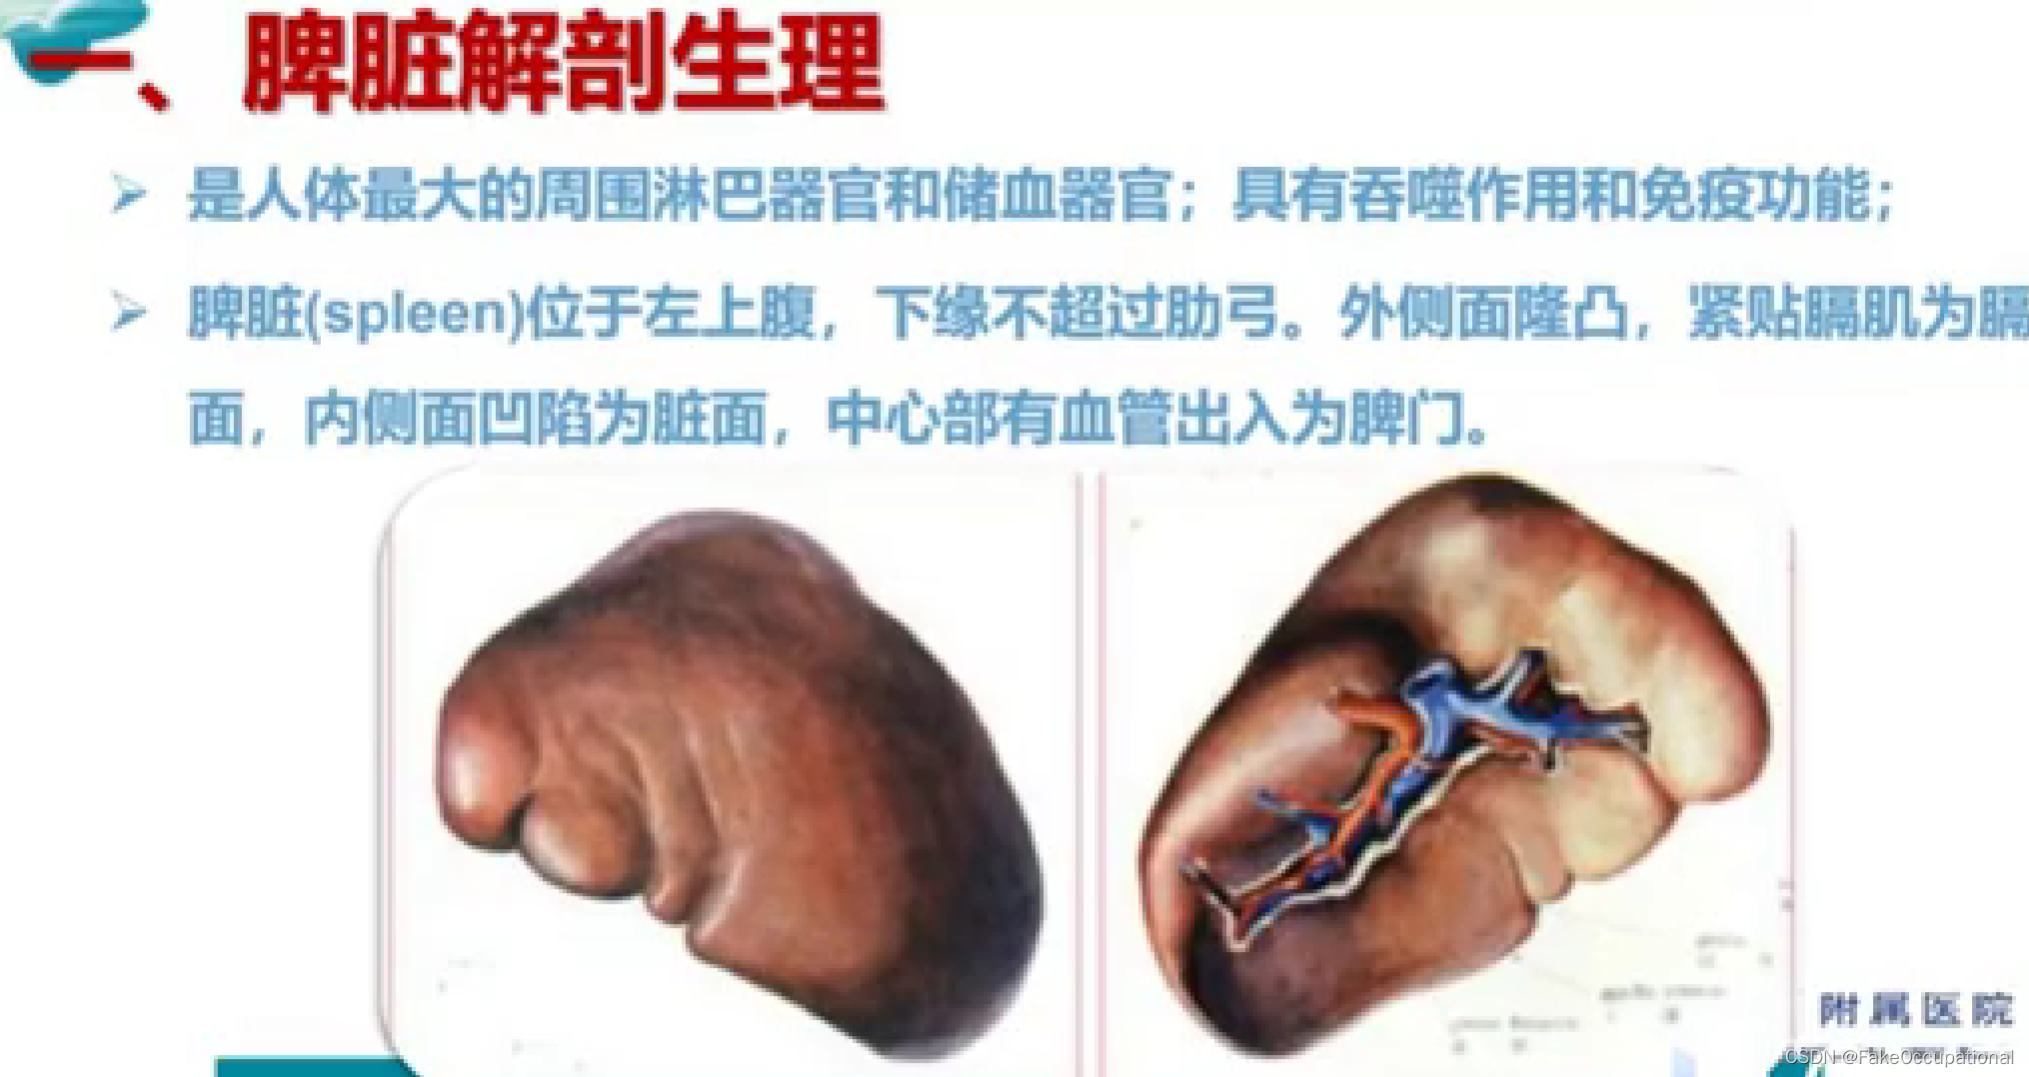

脾脏解剖及正常声像图

脾脏疾病